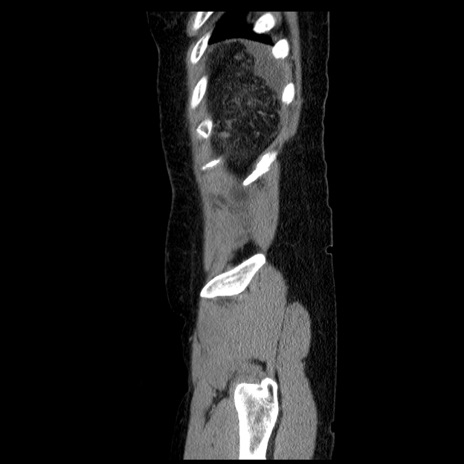

症例6(矢状断像)

横断像

【症例】50歳代女性

【既往歴】卵巣癌術後(8年前に当院で卵巣摘出)

【身体所見】 意識清明、腹部:平坦、腸蠕動音→、やや硬、下腹部自発痛・圧痛あり、反跳痛あり、筋性防御なし。

【データ】WBC 16000、CRP 0.01